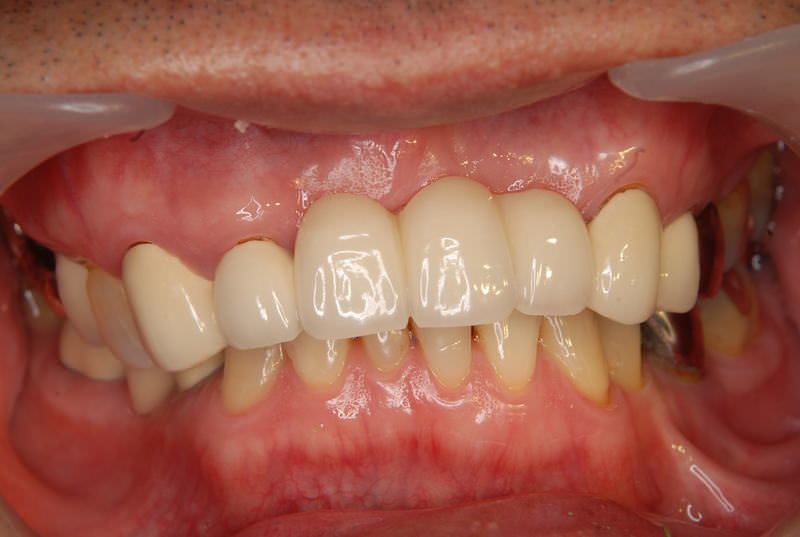

症例2【70代女性】主訴 義歯がわずらわしい・しっかり噛みたい

治療前

治療後(2年経過)

主訴 上顎のみ部分義歯を使用しているが、入れ歯が煩わしい、固定制のインプラントにして欲しいと来院。

左右上顎第一大臼歯相当は、骨の高さが不足しており、ソケットリフト(骨造成)の必要があり、左右第一小臼歯、第一大臼歯支台のインプラントブリッジを提案。

採血で得られた、CGFメンブレンとAFGブロック(人工骨β‐TCPとAFGを混ぜたブロック)を使用し骨を挙上し、インプラントを埋入。

右下のブリッジも、短根歯で動揺が激しい為に抜歯し、インプラント埋入。

上顎の免荷期間は約4ヶ月、下顎の免荷期間は約2ヶ月を経て、仮歯を装着、リハビリをし、メタルボンド(金属焼付ポーセレン)を装着。

費用 280万(オペ・ソケットリフト・人工骨・採血による濃縮血小板生成・仮歯・最終補綴物まで含む)